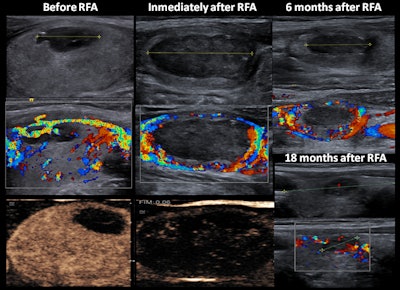

A 27-year-old woman with a solid-cystic nodule had peripheral vascularity and homogeneous enhancement. During follow-up, enlargement of the peripheral residual portion was observed (at six months). At 18 months after RF ablation (RFA), reduction of size and vascularity were observed. All images courtesy of Dr. José Miguel Escudero-Fernández and colleagues.In a digital poster that won a certificate of merit at RSNA 2019, the authors described how they perform RF ablation. They also sought to evaluate the usefulness of contrast-enhanced ultrasonography (CEUS) during RF ablation, assess the value of elastography in the management of nodules, and determine the effects of RF ablation on the immune system.